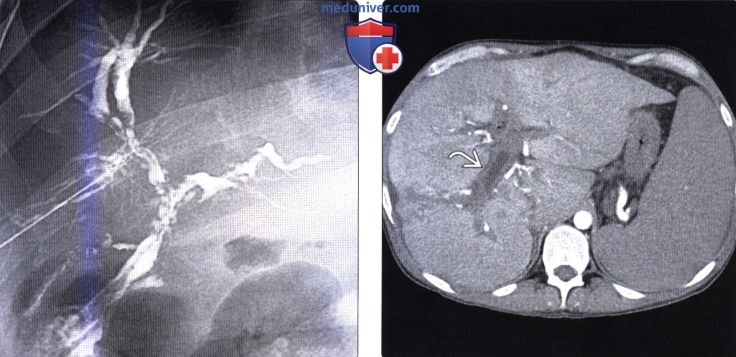

Фотографии и изображения, связанные с симптомами первичного склерозирующего холангита